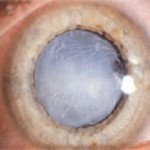

What is Cataract?

Opacification of normally transparent lens of human eye is known as Cataract. The opaque lens does not allow the light rays to pass to the retina so that clear image is not formed over the retina. The patient experiences painless decrease in vision. The objects appear blurred.

CATARACT